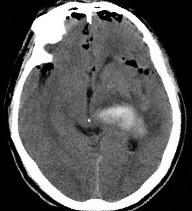

男,32岁,外伤后一天,CT检查如图,下面哪项诊断最恰当()A.脑膜瘤B.脑出血并颅内积气C.脑出血D.颅脑外伤E.颅内积气

问题 男,32岁,外伤后一天,CT检查如图,下面哪项诊断最恰当()

选项 A.脑膜瘤 B.脑出血并颅内积气 C.脑出血 D.颅脑外伤 E.颅内积气

答案 B